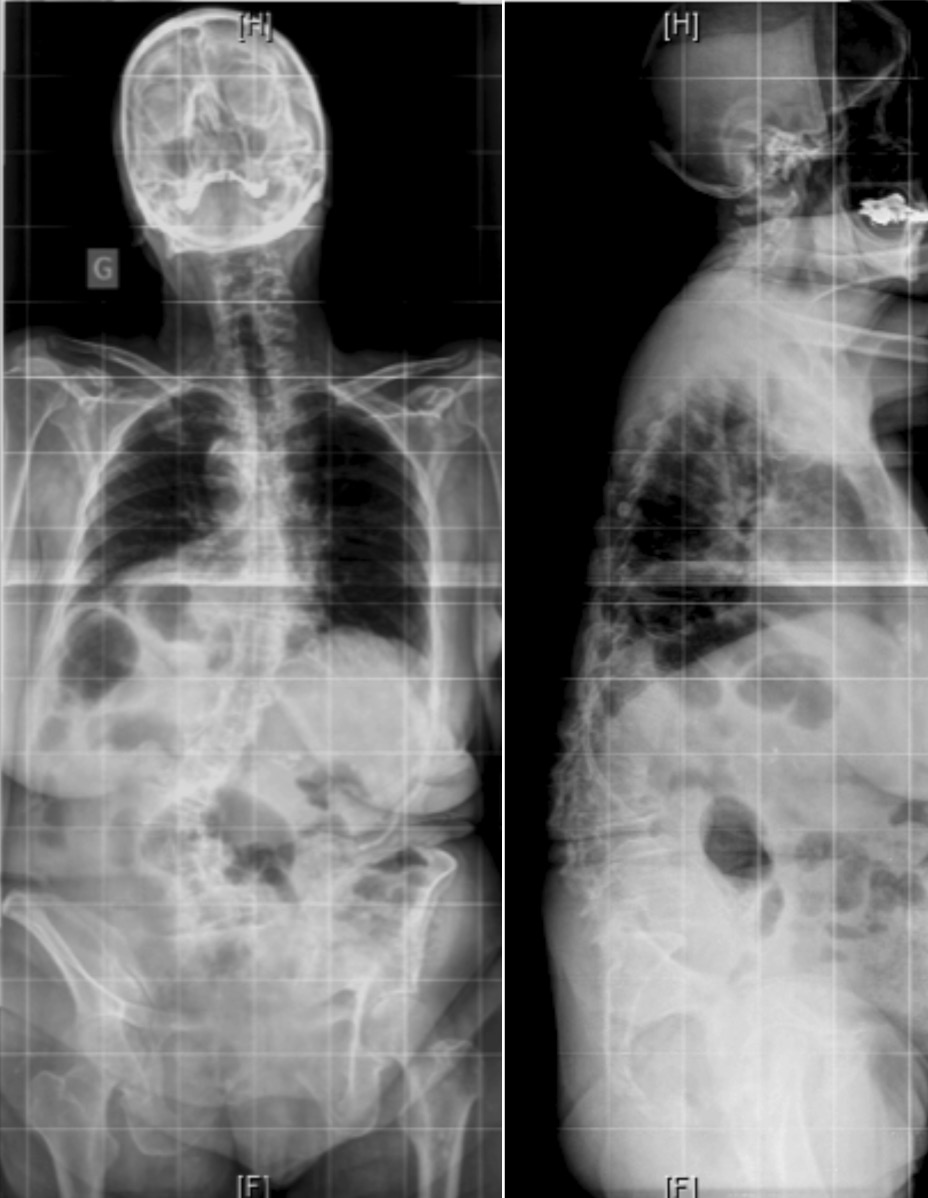

(A)腰椎X线片显示椎体在L1-L2处旋转,椎间盘向凹侧突出,在L2-L3处出现侧向半脱位,椎间盘向凸侧突出;星号表示狭窄部位

(B)轴向MRI显示L2–L3处的凸侧椎间孔狭窄,形成开放性半脱位

(C)L1–L2处的凹侧椎间孔狭窄,形成闭合性半脱位。